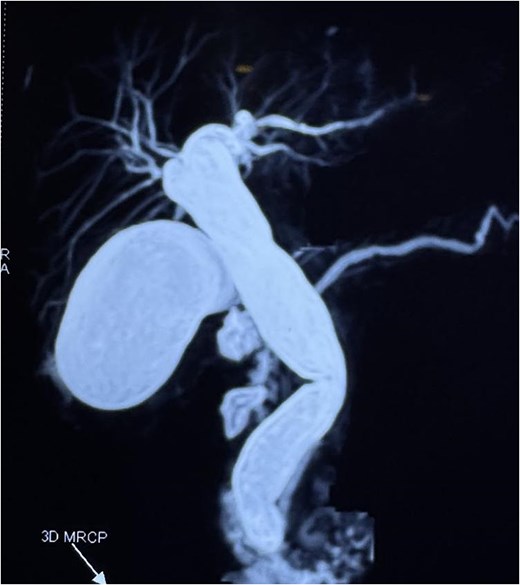

A computed tomography scan confirmed the presence of a duodenal diverticulum (3 cm) in the second part of the duodenum, localized perforation of the gallbladder fundus, and extrahepatic bile duct dilation (Fig. 1). Magnetic resonance cholangiopancreatogram further characterized the findings, revealing biliary stasis secondary to the periampullary diverticulum (Lemmel’s syndrome) without any structural distal obstruction (Fig. 2). Upper gastrointestinal endoscopy excluded periampullary malignancy and confirmed biliary stasis due to the periampullary diverticulum (Fig. 3).

Magnetic resonance cholangiopancreatogram (MRCP) showing biliary stasis without any structural distal obstruction.